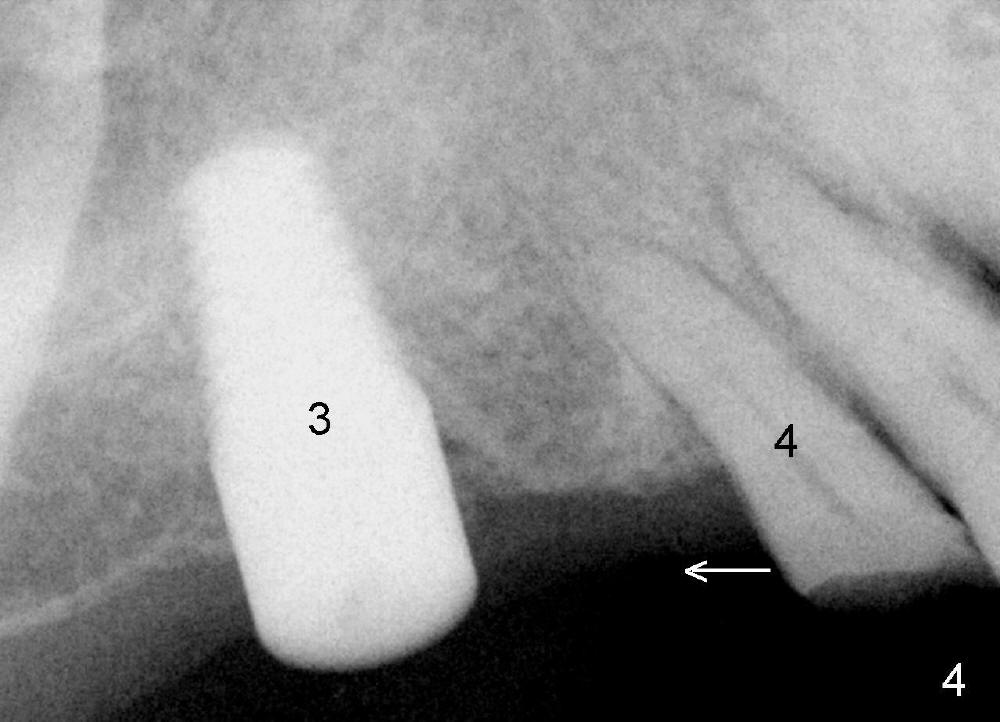

The patient returns for orthodontic treatment 7-8 months post implantation at the sites of #3, 20, 21, and 30 (Fig.4,6,7). He is willing to let the tooth #5 be extracted if necessary, since it has mobility. The tooth is only the functioning posterior tooth in his mouth (Fig.1). It must have occlusal overloading, particularly opposing the implant tooth #28 (Fig.1,7). Multiple implants and ortho treatment appear to be needed.

Clinical exam reveals that the upper midline appears to be deviated to the right (Fig.2), while the left canine relationship is Class II (Fig.3). Therefore, the upper anterior teeth (#9-12) will be moved distally orthodontically. When the tooth #13 is extracted, the immediate implant should be placed more distal than usual. This implant, once osteointegrated, will be used an anchorage for distaliztion of the teeth mesial to it.